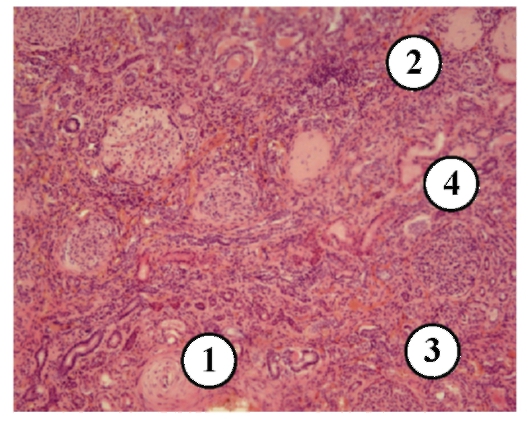

Микропрепараты: Лимфогранулематоз и Нодулярный Склероз

Раздел: Секреты мастерства